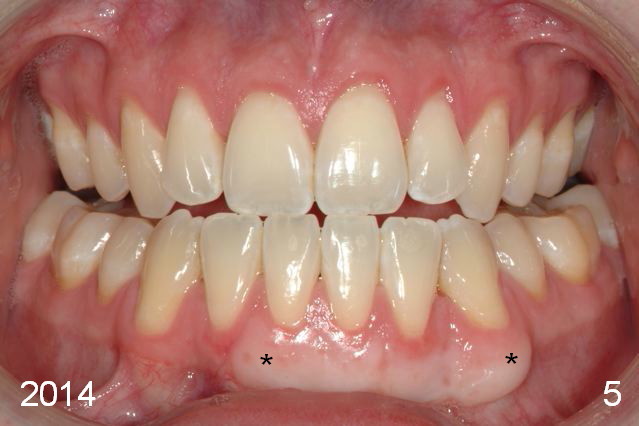

Initial information was obtained on 02/26/2014 (Fig.1-10). Anterior edge-to-edge and Posterior Open Bite (Fig.4 *): unfavorable differential Class III growth after orthodontics as a child.

The labial gingival recession of the lower anterior teeth (Fig.11) was treated with gingival graft (Fig.5,12*). One of the last things Chip Webster did before he died! God rest his soul.